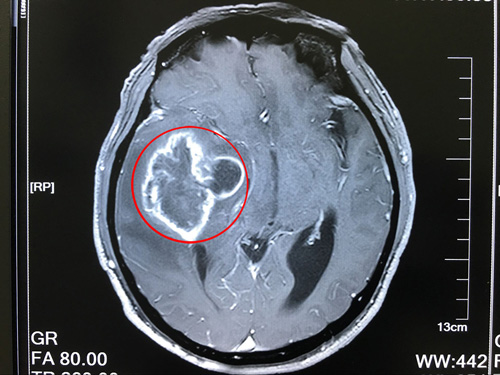

1、头颅MRI:低度恶性肿瘤呈长T1长T2信号,边界清楚,高度恶性肿瘤显示更长T1及T2。少突胶质细胞瘤则显示瘤体边界清楚,几乎无脑水肿,但不能显示钙化。

6、头颅CT:星形细胞瘤多为低密度影,脑室内肿瘤多为高密度影,多形性胶质母细胞瘤多为混杂密度影。注射造影剂后强化扫描定位准确率100%,定性达90%。